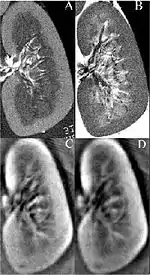

Thermoacoustic imaging was originally proposed by Theodore Bowen in 1981 as a strategy for studying the absorption properties of human tissue using virtually any kind of electromagnetic radiation.[1] But Alexander Graham Bell first reported the physical principle upon which thermoacoustic imaging is based a century earlier.[2] He observed that audible sound could be created by illuminating an intermittent beam of sunlight onto a rubber sheet. Shortly after Bowen's work was published, other researchers proposed methodology for thermoacoustic imaging using microwaves.[3] In 1994 researchers used an infrared laser to produce the first thermoacoustic images of near-infrared optical absorption in a tissue-mimicking phantom, albeit in two dimensions (2D).[4] In 1995 other researchers formulated a general reconstruction algorithm by which 2D thermoacoustic images could be computed from their "projections," i.e. thermoacoustic computed tomography (TCT).[5] By 1998 researchers at Indiana University Medical Center[6] extended TCT to 3D and employed pulsed microwaves to produce the first fully three-dimensional (3D) thermoacoustic images of biologic tissue [an excised lamb kidney (Fig. 1)].[7] The following year they created the first fully 3D thermoacoustic images of cancer in the human breast, again using pulsed microwaves (Fig. 2).[8] Since that time, thermoacoustic imaging has gained widespread popularity in research institutions worldwide.[9][10][11][12][13][14][15] As of 2008, three companies were developing commercial thermoacoustic imaging systems – Seno Medical,[16] Endra, Inc.[17] and OptoSonics, Inc.[18]

- ↑ Kruger RA, Kopecky KK, Aisen AM, Reinecke DR, Kruger GA, Kiser Jr W. Thermoacoustic computed tomography – a new medical imaging paradigm Radiology 1999,211:275-278.